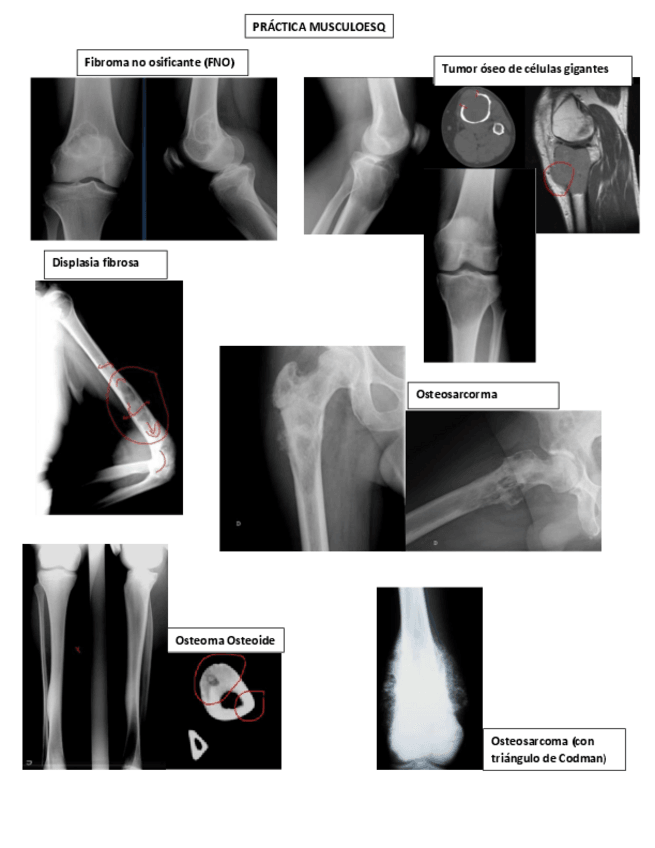

He publicado nuevos practicas de 2º Radiologia General: Practicas-Radiologia.-MSK.pdf

Practica-musculoesqueletico.pdf